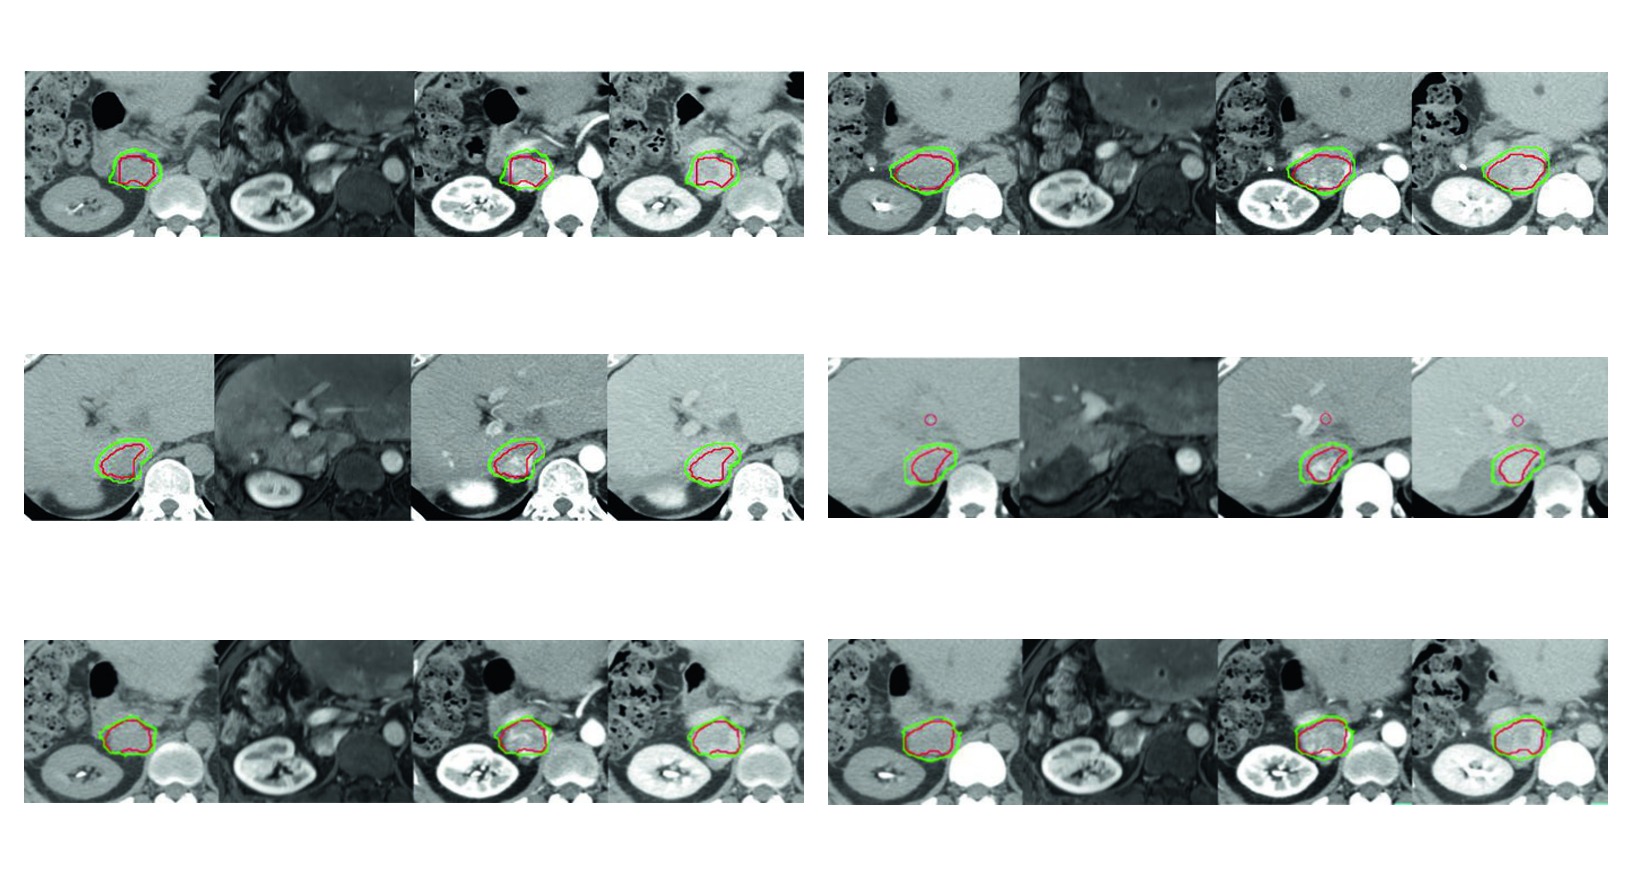

A Figura 17.1 ajuda a enxergar esse raciocinio desde cedo. O caso de tumor residual apos quimioembolizacao arterial transcateter e radiofrequencia mostra que o GTV pode incluir nao apenas o tumor contrastado, mas tambem trombose invadida da veia cava inferior. O CTV, nesse exemplo, recebe margem de 5 mm dentro do limite hepatico e 3 mm ao redor do componente intravascular. O livro nao apresenta a expansao como automatica. Ele mostra uma margem que conversa com a anatomia da recidiva tratada.

As quatro figuras do capitulo funcionam como exemplos aplicados da mesma logica. Todas usam simulacao multiphasica com coordenacao de apneia para imobilizacao do figado. Todas mostram GTV em vermelho e CTV em verde. E todas deixam claro que a margem muda quando entram em cena trombo tumoral, zona previamente ablada, area embolizada ou risco de extensao ao longo do vaso.

Figura 17.1

No primeiro caso, o alvo residual apos quimioembolizacao e radiofrequencia inclui tambem trombose invadida da veia cava inferior. Isso ensina que, quando a doenca ultrapassa o parenquima e entra no compartimento vascular, o planejamento precisa incorporar essa geometria e nao apenas o nodulo hepatico.